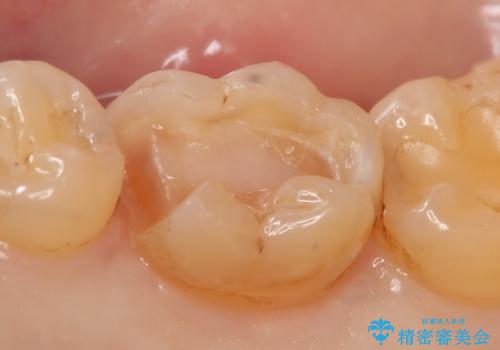

- 右下の銀歯を白くしたいといらっしゃった方の症例です。

銀歯を除去し、セラミックインレーによる修復を行いました。

当院のセラミックインレーはemaxという強度と審美性に優れた材料を使用しています。

またプレス方式でインレーを製作しているため、削り出しで製作するCADCAMより優れた適合性も持ち合わせており、虫歯が再発しにくい修復物です。